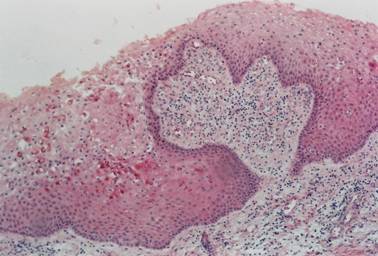

In the correlation between the type of lining epithelium and the stage of rhizogenesis (Table 1), it was found that the enamel reduced epithelium (Figure 1) was the most commonly found type at all stages of rhizogenesis; however, at stages 8 and 9 there was a marked increase in follicles with stratified squamous epithelium (Figure 2), probably owing to a greater maturation of this follicle, such a transformation being expected.

Figure 1

Inactive enamel reduced epithelium (HE / 100X)